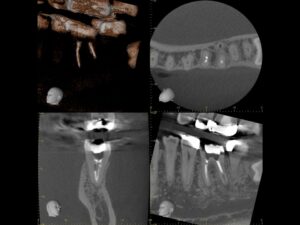

初診時CT。根管治療を何度も繰り返し行ったことで、歯根は無駄に削られて歯質が薄くなり、歯根の先端には穿孔(パーフォレーション)を生じていた。根尖病巣は認めない。

同CT画像。ファイバーコアで土台を補強し、仮歯の状態で3か月の経過観察を行った。初診時にあった歯の違和感は完全に消失したため、オールセラミックで補綴処置を行うこととした。